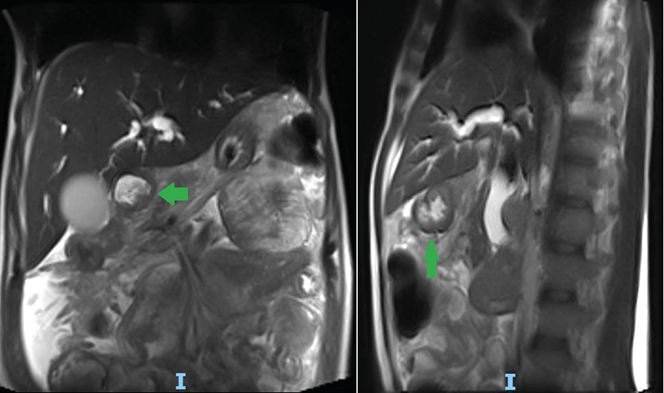

On the second day of admission, a magnetic resonance imaging (MRI) scan of the abdomen showed a mass in the head of the pancreas infiltrating the biliary tract, as well as loss of the cleavage plane with the second portion of the duodenum (Figure 1), which prompted a cholangiogram with bypass of the biliary tract on the fifth day of admission. The following day, follow-up lab tests showed a significant decrease in bilirubin levels (6.39mg/dL), which progressively decreased until normalizing on the ninth day of admission (1.02mg/dL).

Figure 1. MRI of the abdomen with gadolinium-based contrast medium. A) coronal plane; B) sagittal plane.

Note: The arrows show the mass in the head of the pancreas with involvement of the bile duct.